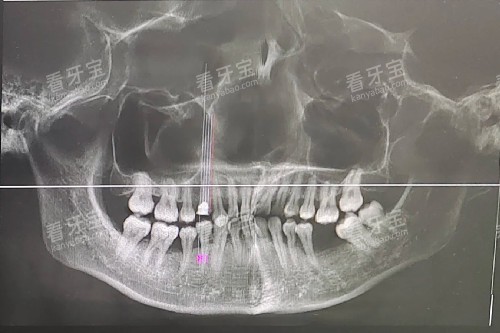

然后敲黑板:如果你有刷牙出血、牙龈退缩、牙齿松动、口臭、牙缝变大这5个症状中的1个以上,别犹豫,赶紧去口腔科!医生会用探针测牙周袋深度、拍X光片看牙槽骨吸收情况,精细判断是不是牙周炎。